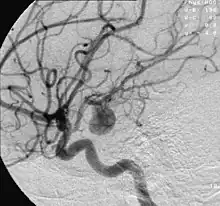

Angiography of an aneurysm in a brain artery. The aneurysm is the large bulge in the center of the image.

Cerebral aneurysms, also known as intracranial or brain aneurysms, occur most commonly in the anterior cerebral artery, which is part of the circle of Willis. This can cause severe strokes leading to death. The next most common sites of cerebral aneurysm occurrence are in the internal carotid artery.[13]